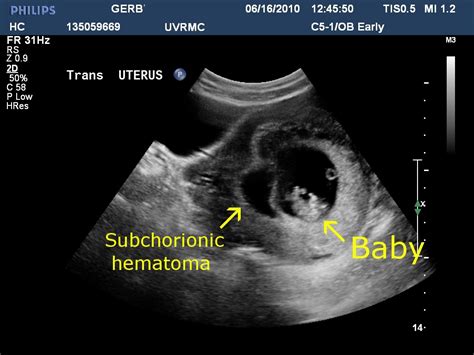

Subchorionic Hematoma Size Chart